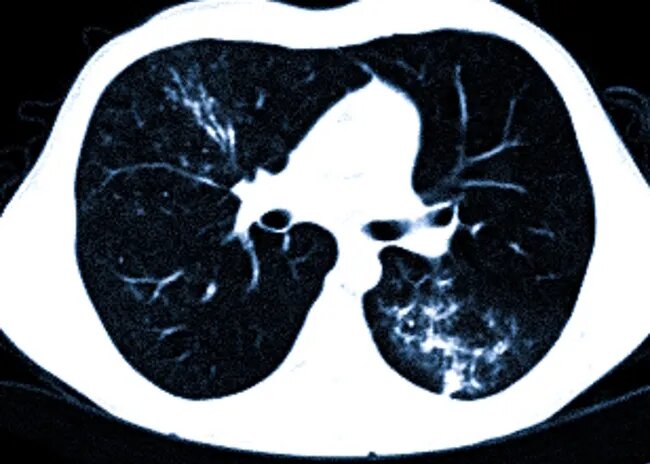

Компьютерная томография (КТ), а точнее ее более совершенный вариант — мультиспиральная компьютерная томография (МСКТ), занимает ключевую позицию в современной пульмонологии. В диагностике пневмоний и их последствий этот метод признан «золотым стандартом», так как обладает уникальной способностью визуализировать мельчайшие структуры легких, недоступные для обычного рентгеновского снимка. Если традиционная рентгенография дает общую картину, часто скрывая детали воспалительного процесса, то КТ позволяет заглянуть вглубь ткани, оценить характер и распространенность патологических изменений с точностью до миллиметра. Это особенно важно, поскольку пневмония — заболевание коварное, способное маскироваться под обычную простуду и быстро прогрессировать, приводя к тяжелым, а иногда и необратимым последствиям.

Основная задача СКТ при подозрении на пневмонию — не просто подтвердить наличие воспаления, но и детально описать его картину. Воспалительный процесс в легких приводит к тому, что альвеолы (воздушные мешочки, отвечающие за газообмен) заполняются жидкостью, слизью или гноем, становясь безвоздушными и нефункциональными. На ранних стадиях, когда симптомы могут быть смазанными (небольшой кашель, слабость), КТ способна выявить участки инфильтрации объемом менее 5% легочной ткани, что делает этот метод незаменимым для ранней диагностики. Чувствительность метода нарастает по мере развития заболевания, достигая 99% к 6-11 дню.

В период пандемии COVID-19 была разработана и внедрена удобная визуальная шкала для оценки объема поражения легких, которая сегодня используется повсеместно. Она позволяет врачам быстро классифицировать тяжесть состояния:

КТ-0: Признаков пневмонии нет.

КТ-1 (легкая степень): Поражено менее 25% объема легочной ткани. Характерны небольшие участки уплотнения по типу «матового стекла».

КТ-2 (умеренная степень): Поражение составляет от 25% до 50%. Обнаруживаются множественные участки «матового стекла».

КТ-3 (среднетяжелая степень): В патологический процесс вовлечено от 50% до 75% легких. Появляются участки консолидации (более плотного уплотнения), когда ткань легкого по плотности приближается к ткани печени.

КТ-4 (тяжелая, критическая степень): Поражено более 75% легочной паренхимы. Легкие теряют свою воздушность, визуализируются диффузные уплотнения, симптом «булыжной мостовой» и другие тяжелые изменения.

Важно понимать, что эта классификация отражает не только объем, но и прогноз. Переход от стадии КТ-3 к КТ-4 происходит очень быстро и несет прямую угрозу жизни, требуя немедленной респираторной поддержки.